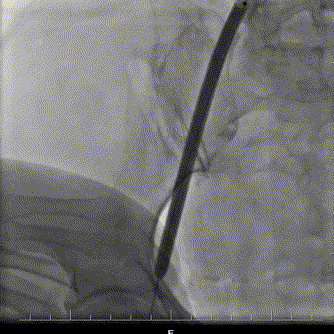

髂外动脉狭窄

16扩张鞘扩张

沿导丝送入一枚60*120mm高压球囊于狭窄段7atm*120s扩张,AL1、AL2直头导丝跨瓣,测量压力阶差80mmHg,置于超硬导丝到左心。

60x120mm7atm*120s扩张